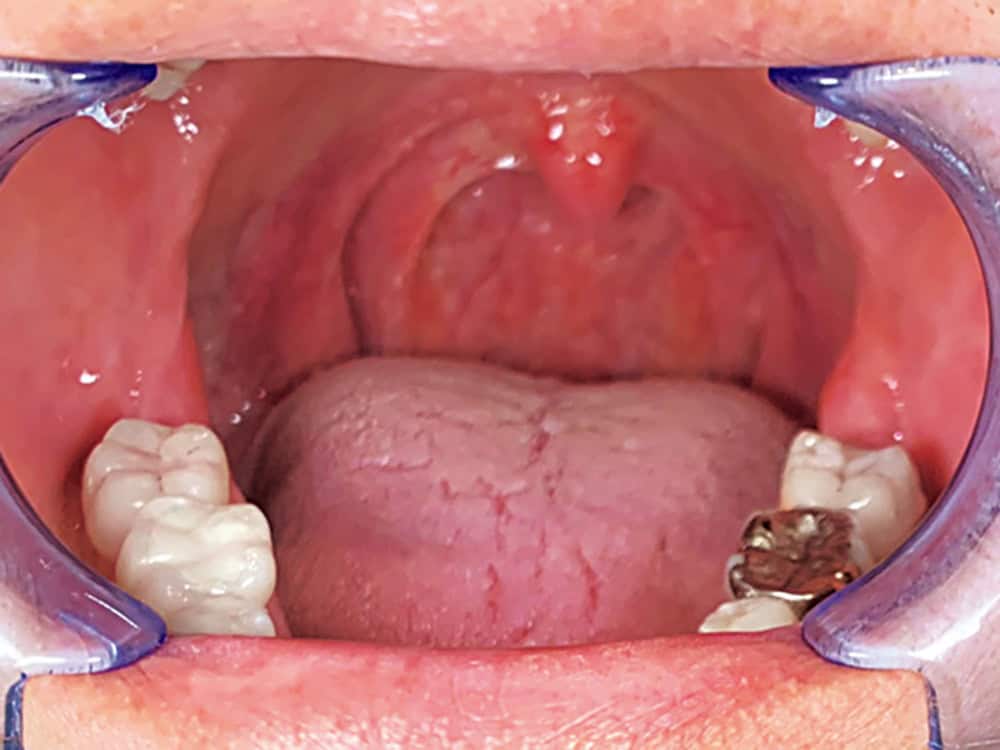

① 舌を吸い上げて上あごにくっつける

口を開けて舌全体を上顎に吸い上げて20秒キープする。舌裏に洞窟を2つ作り、2分間繰り返す。